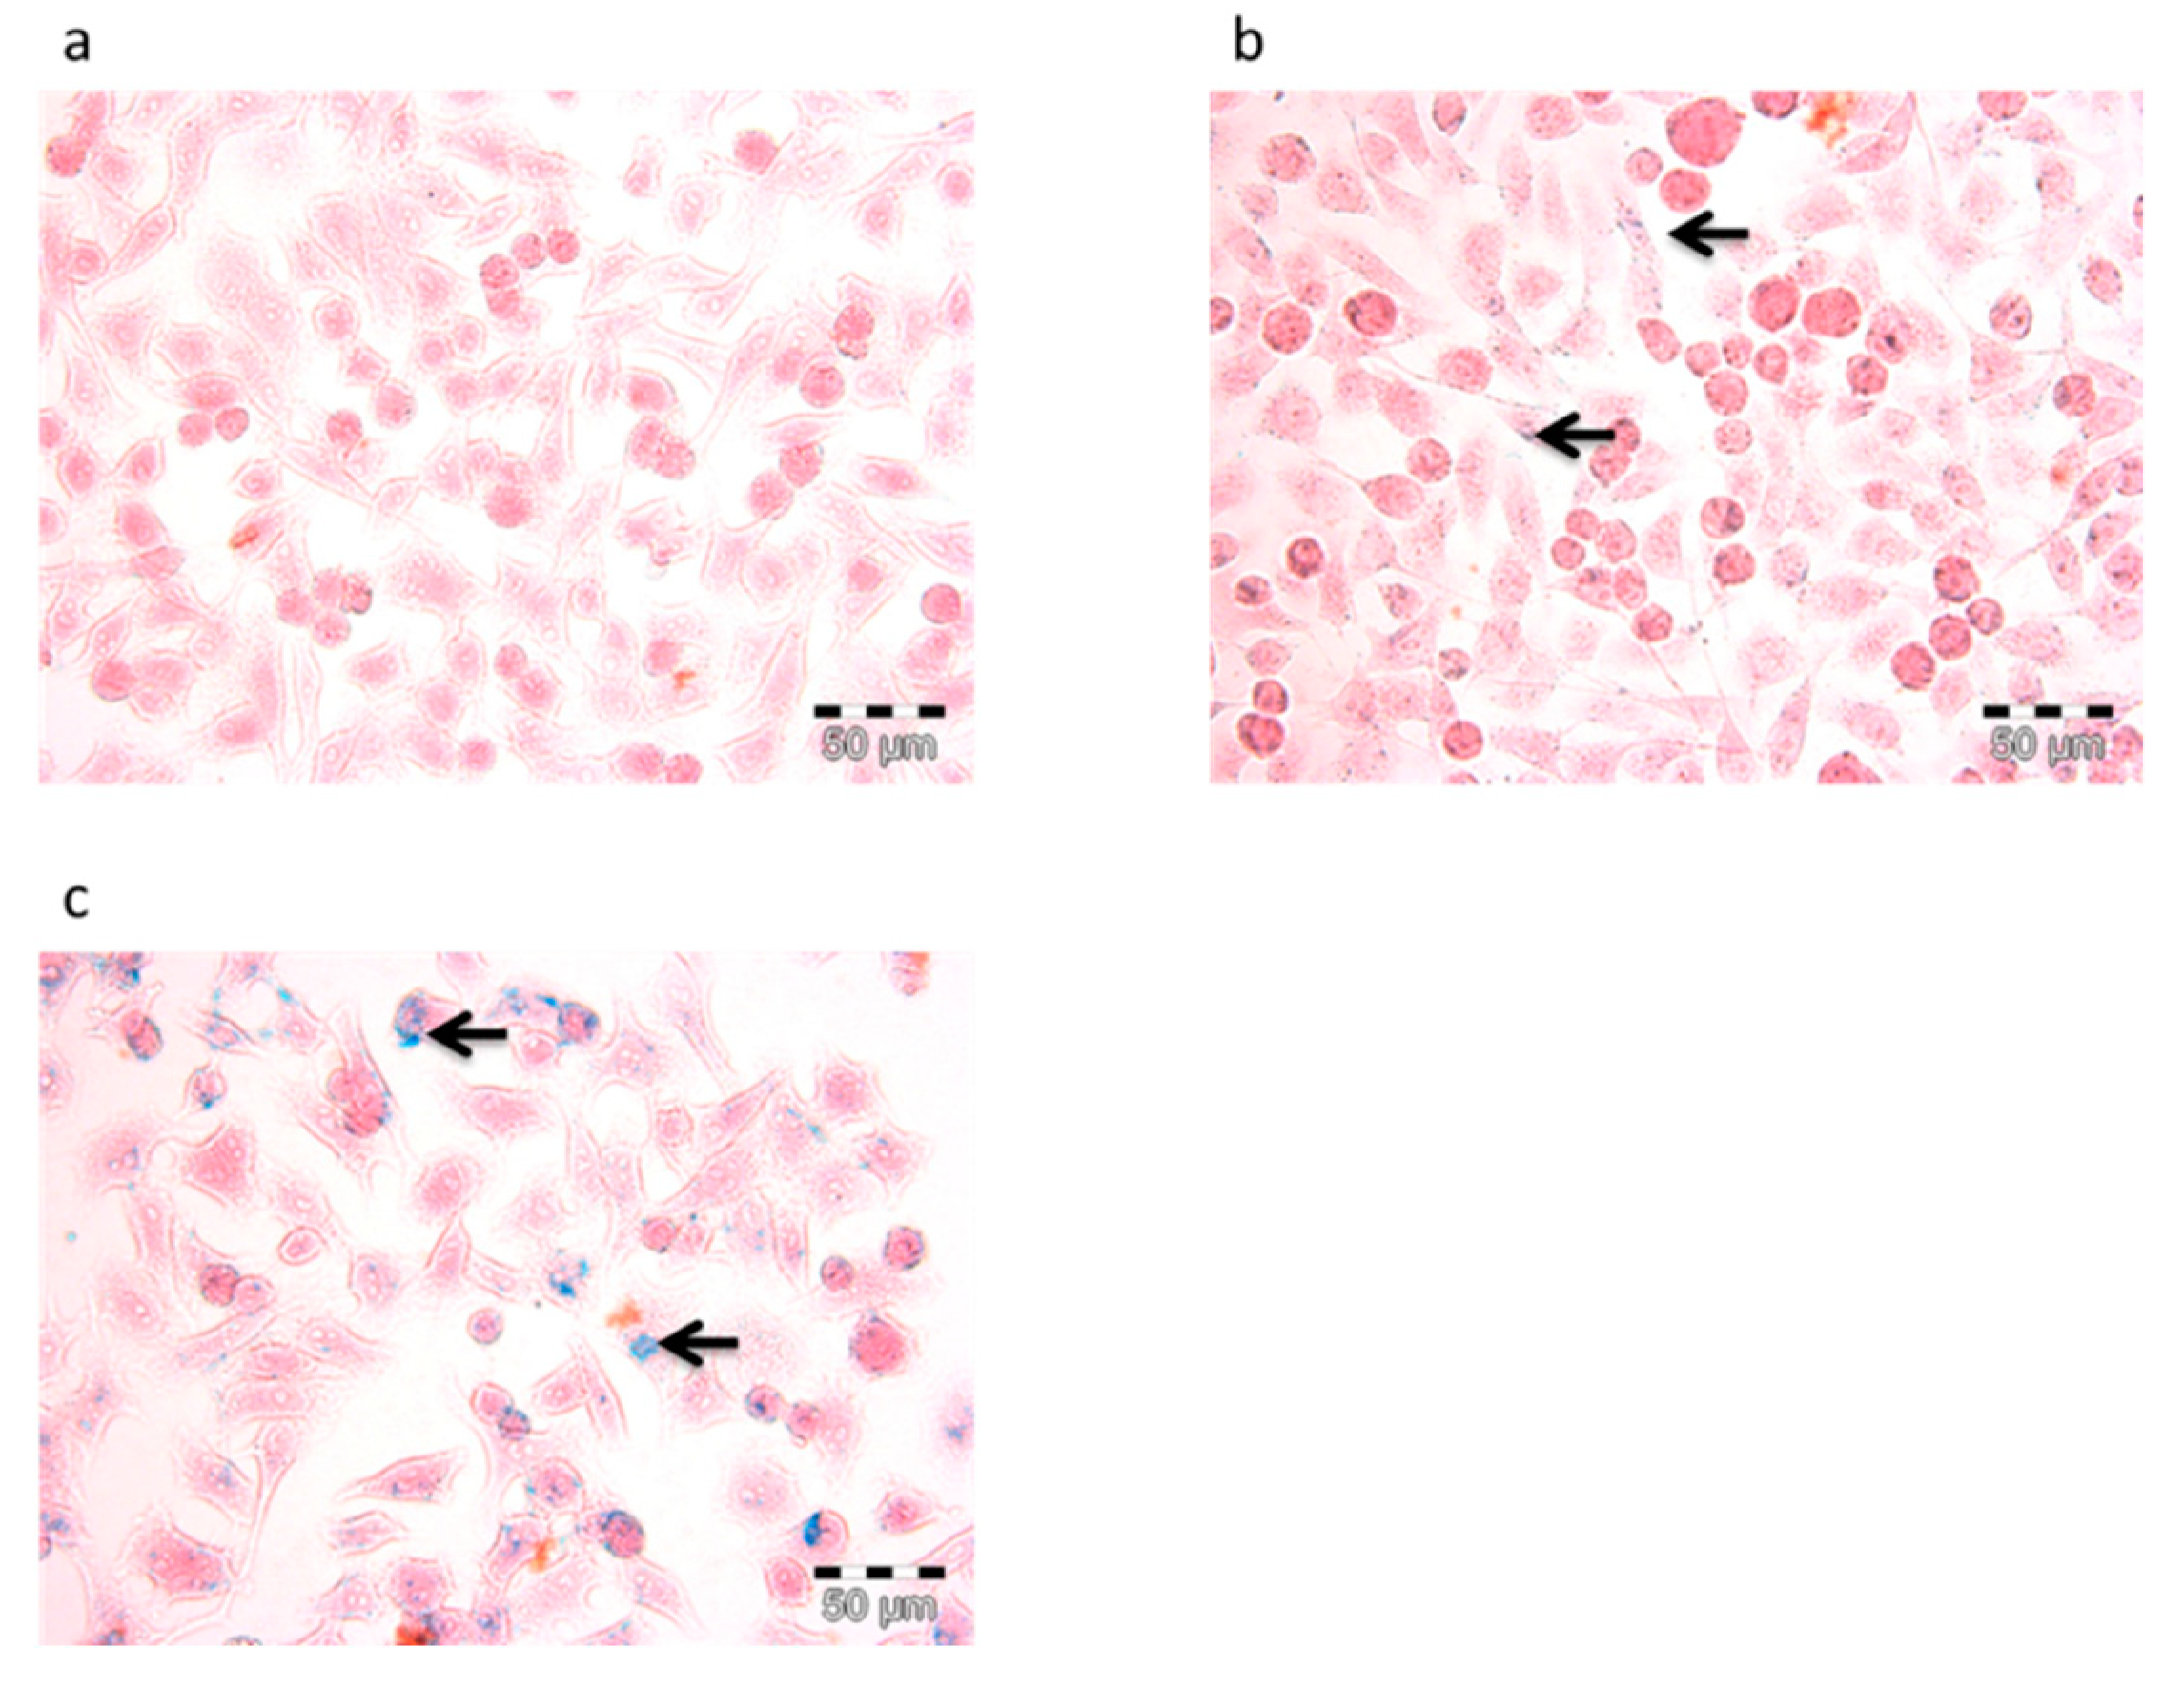

3.4.1. Prussian Blue Staining and Confocal Laser Scanning (CLSM)

3.4.2. Iron Concentration Measurement and Flow Cytometry Assays (FACs)